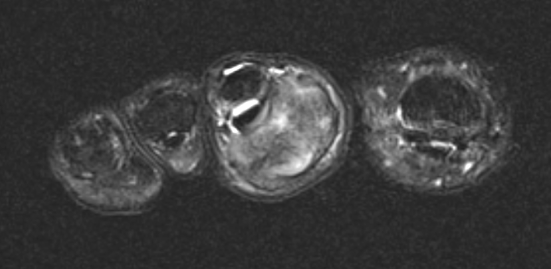

GCT of tibialis posterior tendon sheath

- heterogenous mass on MRI

- biopsy - abundant giant cells